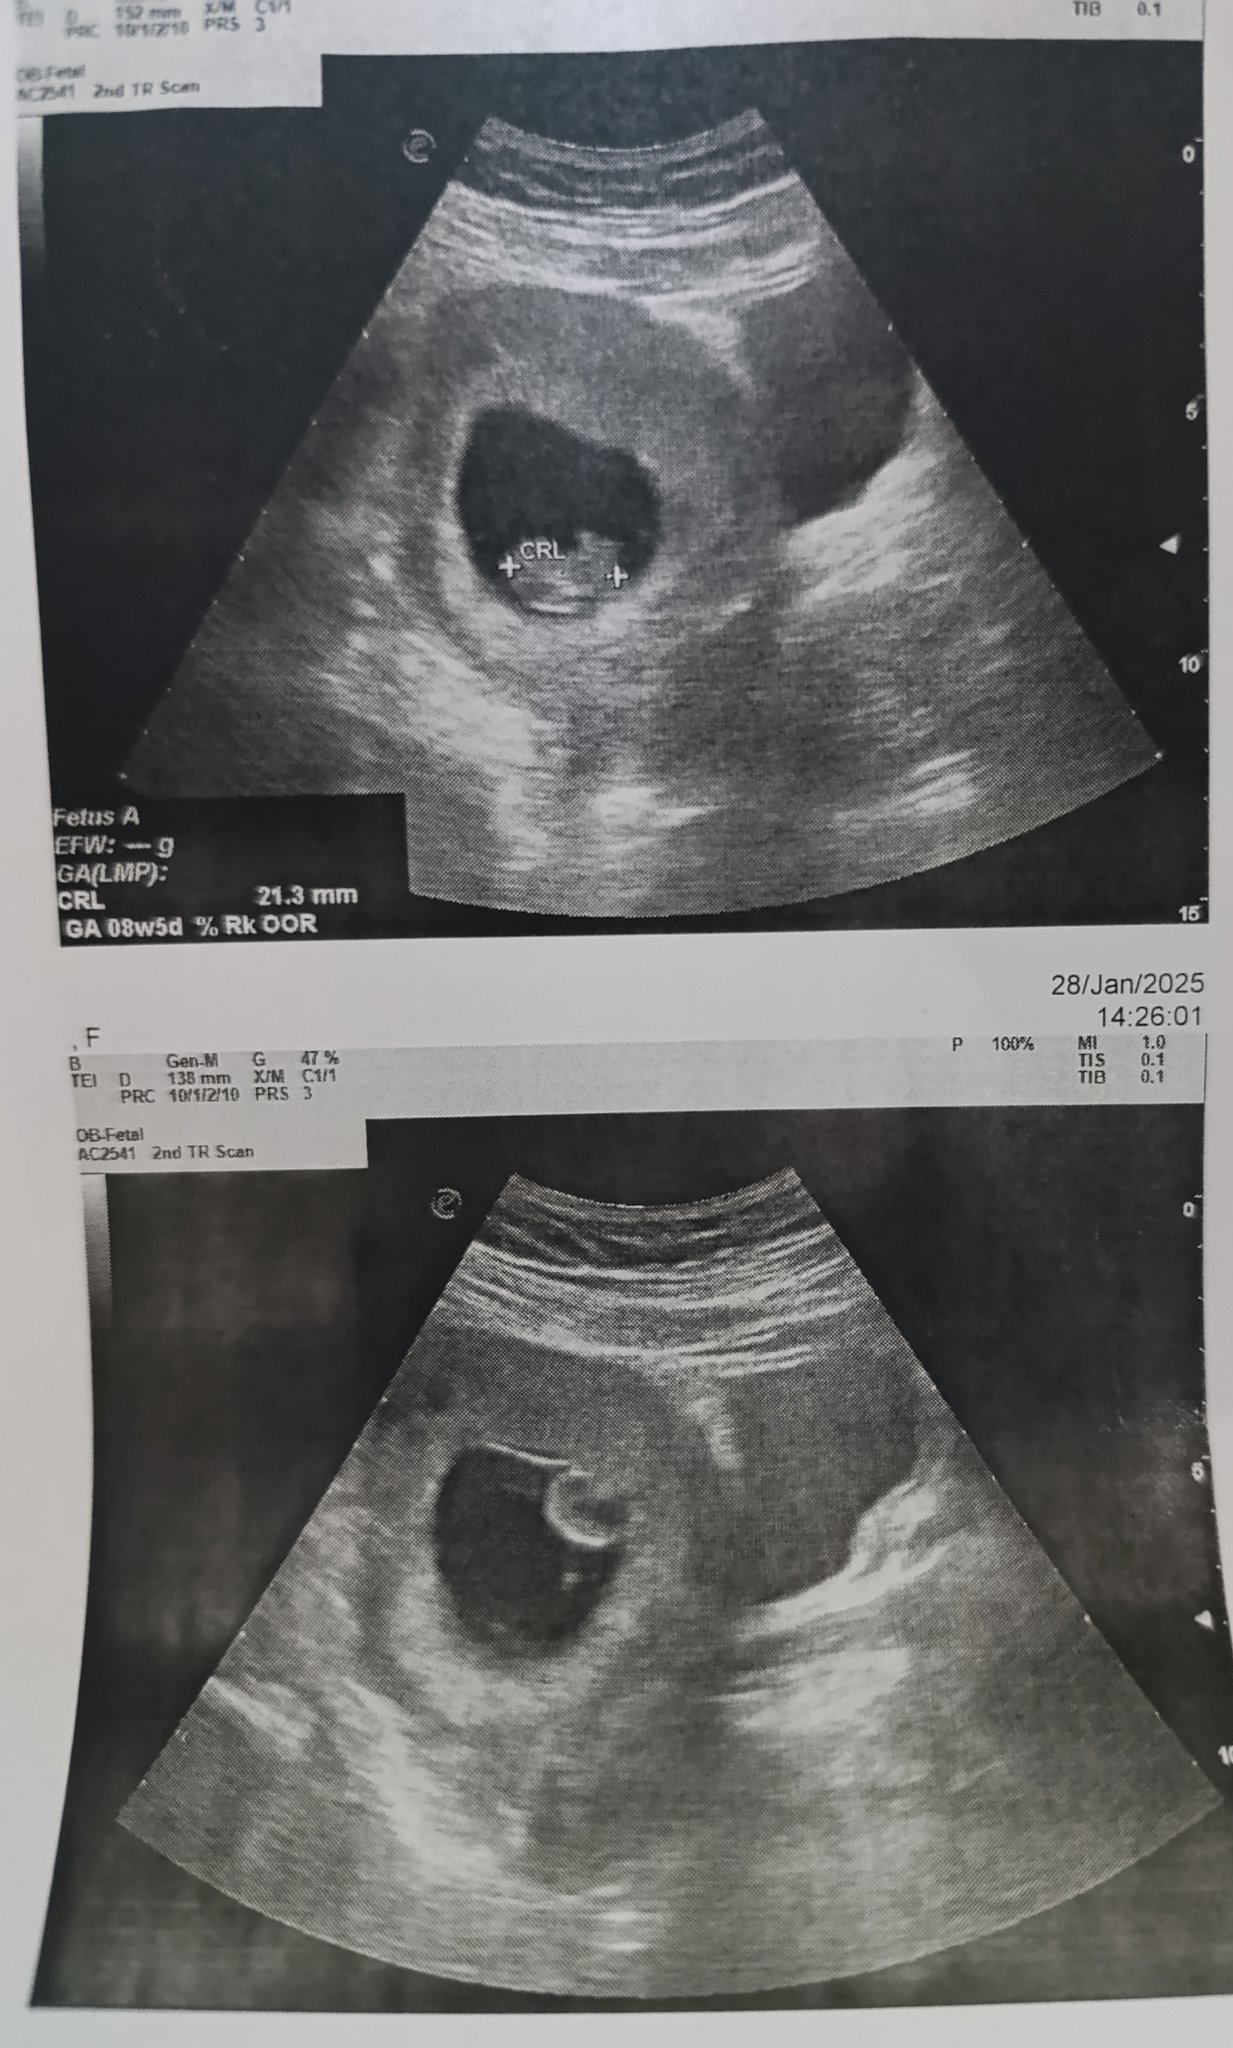

Синдромът на изчезващия близнак е медицинско състояние, при което единият от близнаците се абсорбира от тялото на другия и изчезва. Това може да се наблюдава по време на ултразвукови прегледи, където един плод изглежда е изчезнал, но все още могат да бъдат открити остатъци. В случаите на синдром на изчезващия близнак оставащият плод обикновено продължава да се развива нормално.